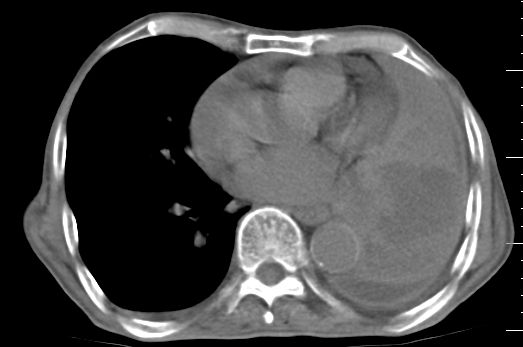

标题: CT10141:男、84岁,咳嗽、咯血1年。 [打印本页]

标题: CT10141:男、84岁,咳嗽、咯血1年。

支持左侧中央型肺癌伴下叶肺不张\\纵隔淋巴结转移.左侧包裹性胸腔积液\\心包积液.左侧少量胸腔积液..慢性支气管炎伴部分间质纤维化.

咯血病史较长,左肺下叶实变,体积未明显缩小,隐约可见血管影及坏死阴影,双肺门及纵隔淋巴结增大,心包增厚积液,纵隔右移位,单侧胸腔积液,首先考虑:大叶型肺泡癌伴纵隔心包转移。